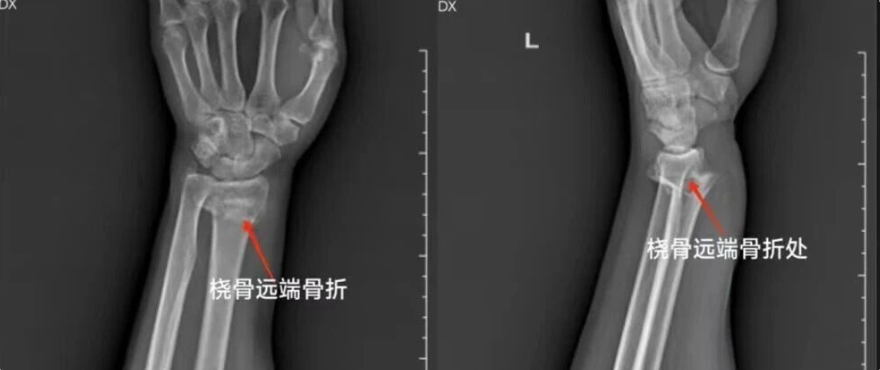

桡骨远端骨折的诊断与治疗